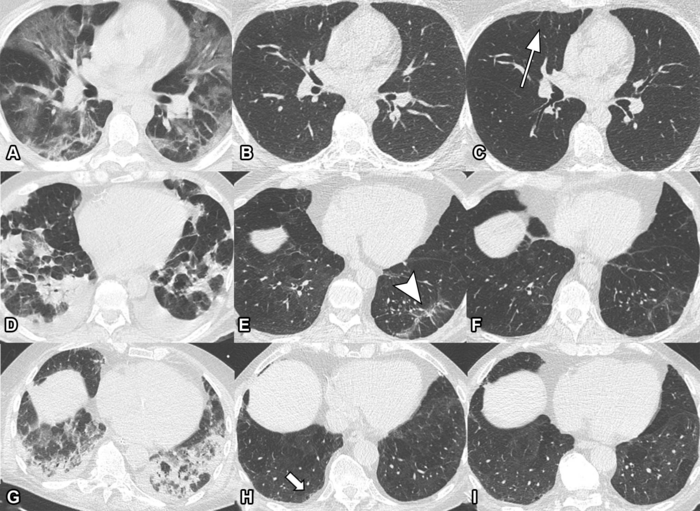

Serial non-contrast axial chest CTs of three study participants with prior COVID-19 pneumonia. Chest CT of a 44-year-old man (upper row, A-C) displayed extensive bilateral GGO and supleural reticulation during acute COVID-19 (A). At the 2-month follow-up almost complete resolution of GGO with residual subpleural reticulation in the middle lobe was noted (B). These subpleural reticulations (arrow) persisted up to one year after onset (C). Chest CT of a 68-year-old-man (middle row, D-F) demonstrated patchy bilateral consolidations, a subpleural arcade-like sign and pleural effusions during active infection (D). At the 2-month follow-up, a substantial improvement of OP pattern was noted with GGO and subpleural reticulation including arcade-like sign (arrowhead) in the left lower lobe (E). At the 1-year follow-up, further improvement was noticed. However, subtle reticulation and GGO could still be detected (F). Chest CT of a 79-year-old man (lower row, G-I) displayed bilateral consolidations and small areas of GGO while admitted to the ICU (G). At the 2-month follow-up, residual GGO and small subpleural microcystic changes (thick arrow) were noticed (H), which persisted up to 1 year after onset (I). Image courtesy of the Radiological Society of North America